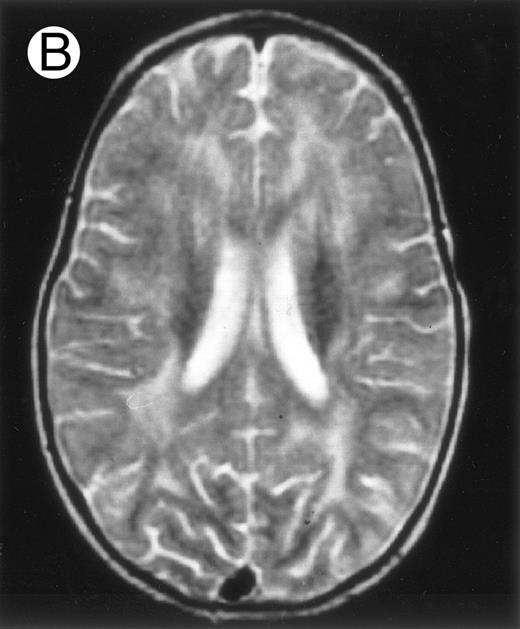

Three different aspects of brain imaging in HLH patients. (A) CT scan of a 3-month-old baby showing a large subdural effusion, several necrotic areas and hypodensities of the white matter. (B) Brain magnetic resonance of a 14-month-old boy showing large confluent areas of hypersignal in T2-weighted images. (C) Large symmetrical necrotic areas of cerebellar white matter in a 41/2-year-old girl (MRI).

Among the nine children with initial neurological symptoms, seizures were the most frequent initial symptom in the youngest patients, whereas ataxia was found in the two oldest patients (46 and 58 months old, respectively) (Table 1). All nine patients had the same CSF abnormalities as patients with meningitis only. Eight of these nine patients had a neuroradiological study performed at the time of their first neurological symptoms (Table 1). The two most frequent lesions were focal necrosis with parenchymal volume loss and atrophy (Fig 2A and C) and white matter abnormalities (Fig 2B). Several small focal lesions with hypersignal at MR imaging that enhanced after administration of gadopentate dimeglumine (or contrast on CT scan) were also observed in two cases.